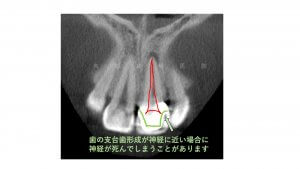

では違和感が出た原因はなんでしょうか?歯科用CBCT検査を撮影してみると根尖部に限局した透過像が認められました。下の写真で矢印で記した部位です。

診断名は根尖性周囲炎と言われ、一般的にはいわゆる歯の神経が死んだ状態です。ではなぜ歯の神経が死んでしまったのでしょうか?

歯の内部には歯髄と言われる組織がありますが髄角と言われる部分が歯の外側へ突出しているため歯を削る時に歯髄に近くなる場合があります。

特にセラミック治療では被せ物の厚みを確保するために切削量が増える傾向にあります。

今回の症例でも切削量が増え歯髄の髄角に近づいたために術後何年かかけてゆっくり歯髄が失活したと考察しました。